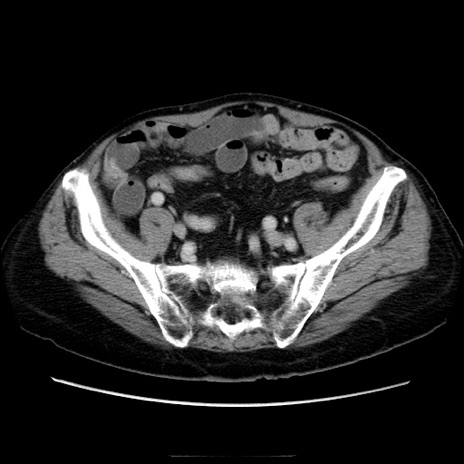

冠状断像